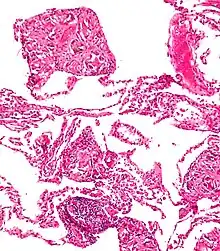

A foreign body reaction (FBR) is a typical tissue response to a foreign body within biological tissue.[1] It usually includes the formation of a foreign body granuloma.[2] Tissue encapsulation of an implant is an example, as is inflammation around a splinter.[3] Foreign body granuloma formation consists of protein adsorption, macrophages, multinucleated foreign body giant cells (macrophage fusion), fibroblasts, and angiogenesis. It has also been proposed that the mechanical property of the interface between an implant and its surrounding tissues is critical for the host response.[4]